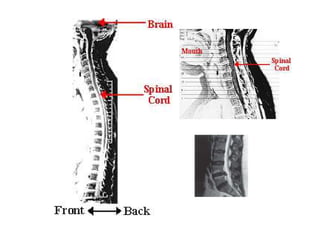

Spinal cord

Features of the spinal cord.

Medula Espinal

• Estende-se do tronco encefálico até o cone medular (término em L1)

dentro do canal vertebral, no qual está protegida.

• Apresenta um revestimento em camadas (membranas): dura-máter,

aracnóide-máter e pia-máter.

• É formada por múltiplos tratos e colunas ascendentes (sensitivas) e

descendentes (motoras).

• Apresenta-se mais alargada nas regiões cervical e lombar da coluna

vertebral, onde as raízes formam plexos para inervarem as extremidades

superiores e inferiores.

• Raízes dos nervos espinhais pares (direita e esquerda) emergem de cada

nível vertebral. As raízes dos nervos espinhais são formadas por

componentes anteriores (motores) e posteriores (sensitivos).